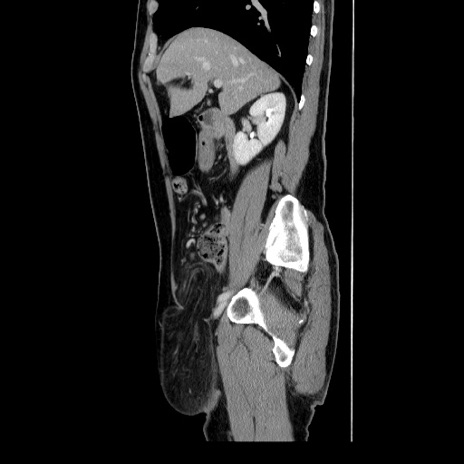

冠状断像

【症例】60歳代 男性

【主訴】右鼠径部膨隆

【現病歴】1年程前より右鼠径部膨隆あり。自己にて還納可能だったため放置していた。3時間前より右鼠径部の脱出を認め、還納困難となり受診。

【身体所見】右鼠径部に小児頭大の膨隆あり。弾性硬であり、用手還納は困難。左鼠径部にも膨隆を認める。脱出はなし。